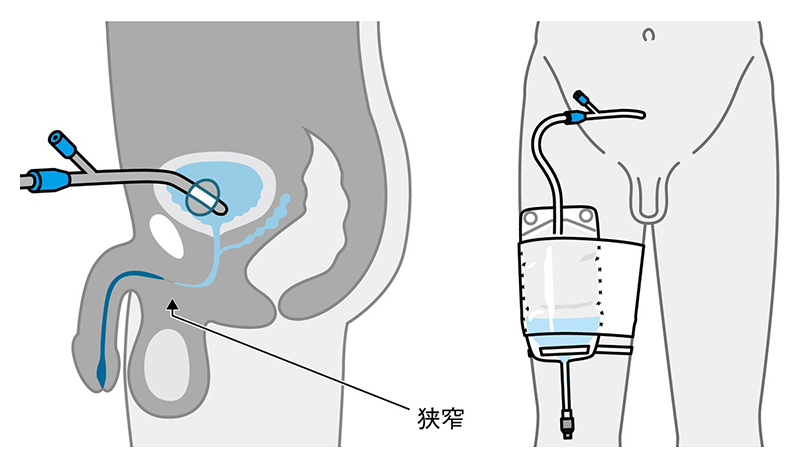

尿道狭窄症とは 堀口明男 Official Site

尿道狭窄症とは 堀口明男 Official Site

尿道形成術とは 堀口明男 Official Site